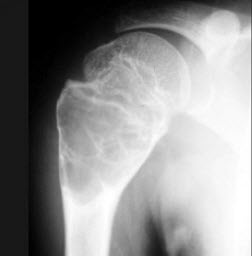

男,15岁,右肩疼痛1月余,结合图像,最可能的诊断是()

A.嗜酸性肉芽肿

B.动脉瘤样骨性囊肿

C.骨样骨瘤

D.血管瘤

E.以上都不是